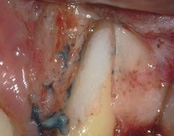

This person had root canal therapy many years ago. One root had excess material outside of the root preventing healing. Another root had a perforation (a hole) and a crack. The large root had a post and had not healed from the initial root canal treatment.

The post was removed, that root was retreated. The root with the excess material, an apicoectomy was done, the excess material, and infection cleaned out. The root with the perforation and crack was removed. The tooth healed and is still in function. This area is a poor area for an implant.